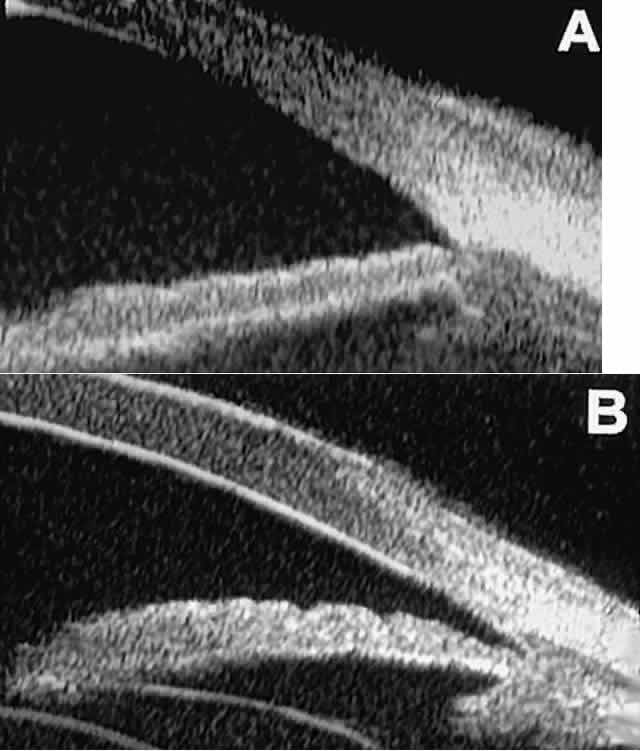

TRAUMA

After blunt ocular trauma, UBM can be used to evaluate iris-angle abnormalities associated with and possibly obscured by hyphema, including angle recession and cyclodialysis, and to illustrate the presence and extent of blood clots.4 Angle recession is characterized on UBM (Fig. 21A) by posterior displacement of the point of attachment of the iris to the sclera. In the acute stage, the post-traumatic recess is usually filled with blood. Cyclodialysis (described and illustrated earlier) appears on radial UBM slices through the limbal region (see Fig. 13B) as a fluid-filled cleft between the sclera and ciliary body.13 This abnormality is by definition associated with at least a localized ciliochoroidal effusion.

Fig. 21. UBM features of ocular trauma. A. Angle recession with traumatic hyphema after blunt injury. B. Intracorneal foreign body (rose thorn fragment). Note inflammatory cells in adjacent aqueous. C. Intraocular foreign body (glass fragment in inferior angle).

After ocular perforations, lacerations, and intraocular surgery, UBM can show abnormalities such as retained foreign bodies too small to be imaged by other technologies.3,4 Foreign bodies appear on UBM (Fig. 22A and B) as highly reflective focal lesions that are frequently associated with inflammatory features.

Fig. 22. UBM features of primary neuroepithelial cysts of iris and ciliary body. A. Primary neuroepithelial cyst of iris midzone. B. Primary neuroepithelial cyst of iridociliary sulcus. C. Multiple neuroepithelial cysts of peripheral iris and ciliary body. D. Neuroepithelial cysts of pars plana of ciliary body shown in circumferential slice.